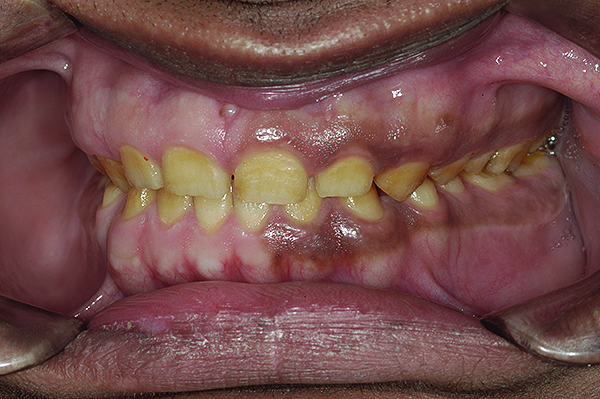

The authors report on a 21-year-old patient who presented with severe discoloration and mild sensitivity of teeth (Figure 1). The teeth visible in his smile were very short, unsightly, and unbecoming for his age.

A thorough clinical examination and analysis were carried out to assess the esthetic and functional problems of the patient (Figure 2 through Figure 7). The medical history was non-contributory, except for mild leukoderma. Temporomandibular joint (TMJ) function was within normal range.

Mounted study casts were used to evaluate occlusion. The relevant findings were as follows2: Facial analysis revealed a canted maxillary occlusal plane and canted dental midline. Dentolabial analysis showed that the maxillary incisors were not adequately visible during repose; it also revealed a reverse smile line, as well as a wide smile showing 12 teeth. Results from the phonetic analysis were that “F” and “V” sounds revealed upper incisal shortening, “M” and “S” pronunciation disclosed a diminished vertical dimension of occlusion (VDO), and “E” sounds showed severe shortening of incisors. Dental analysis revealed thick biotype, asymmetry and inappropriate location of gingival levels and zenith, incorrect axial inclinations, a displeasing width-to-length ratio, and pitted surfaces on most teeth. Interproximal decay was evident on several posterior teeth, as revealed by radiographic analysis. Finally, occlusal examination indicated discrepancy between maximum intercuspation (MIP) and centric relation (CR) as well as a lack of anterior guidance/posterior disclusion.